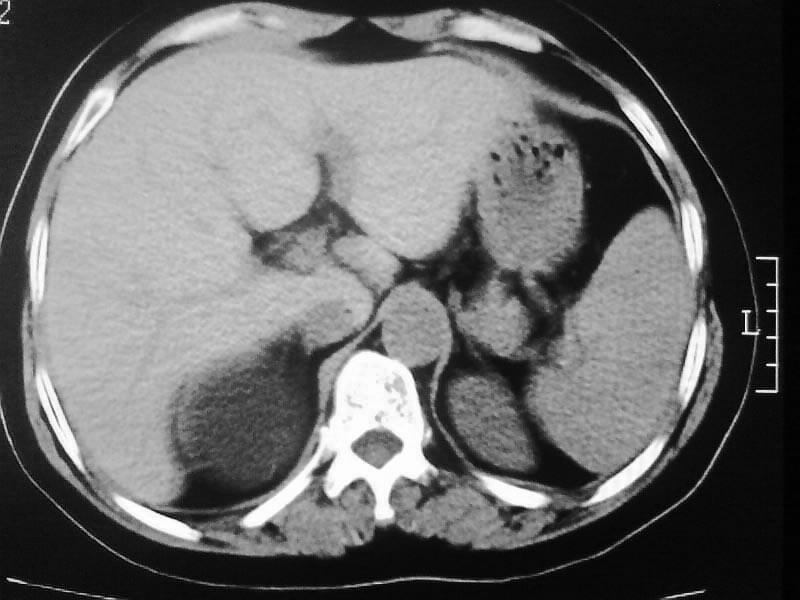

标题: CT20044:女,45岁,腰痛2年,双肾结石,右输尿管结石,右肾重度积 [打印本页]

标题: CT20044:女,45岁,腰痛2年,双肾结石,右输尿管结石,右肾重度积

其内见多房性分隔考虑多囊肾

左侧输尿管上段结石

支持双肾结石、右输尿管上端结石,右肾重度积水

右肾梗阻性积水。

支持 右肾结石、右输尿管上端结石,右肾重度积水。